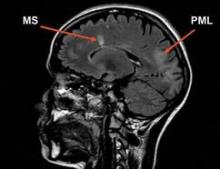

Courtesy Biogen Idec

Sagittal FLAIR (Fluid Attenuated Inversion Recovery) MR image of a patient with MS and PML.